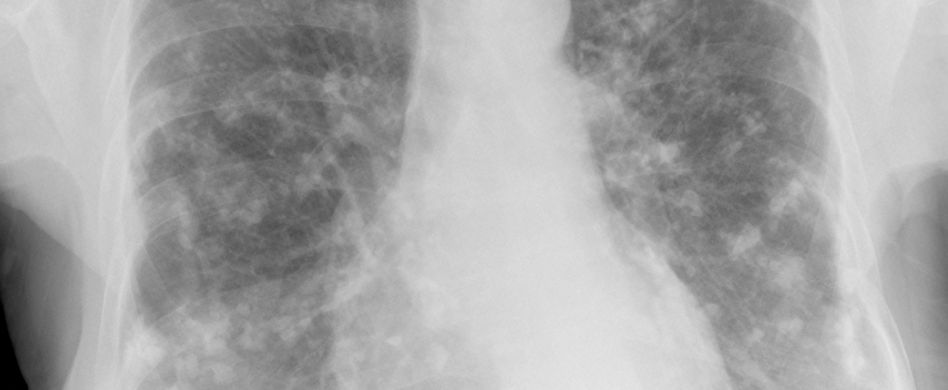

Die Lunge auf natürliche Weise entgiften. Spannende Fakten rund um die Lunge. Bei kurzfristigen Entzündungen des Lungengewebes löst sich das verdickte Gewebe wieder vollständig auf.

Dementsprechend werden die Auswaschungsdefizite der Nährstoffe auf ein niedriges Niveau gebracht und der Rasendünger löst sich leichter auf. Mit jedem Atemzug wird ungefähr ein halber Liter Luft durch die Lunge gepumpt. Bei langfristigen Entzündungsprozessen in der Lunge wie sie etwa durch ständigen Kontakt mit Asbest verursacht werden können kann die Verkalkung mit den Jahren deutlich zunehmen und die Lungenfunktion.

Die meisten Fremdkörper können durch Husten wieder aus der Lunge herausbefördert werden. Bei einem Lungenemphysem lösen sich Wände zwischen ihnen nach und nach auf. Neues Album Denen Die Wir Waren erhältlich ab 26052017. Dies hat verschiedene Gründe. Eine gesunde Lunge besteht aus rund 300 Millionen Lungenbläschen. Durch dieses tritt Luft aus die sich neben der Lunge ansammelt. Ein Lungenemphysem führt dazu dass die Lunge. Wenn Fett abgebaut wird wandelt der Körper es hauptsächlich in das Gas Kohlendioxid um das anschließend mit der Atmung ausgestoßen wird. Noch besser funktioniert das wenn nach der Einatmung eine kurze Atempause wenn möglich langsam bis drei zählen eingehalten wird.

Chronic obstruktive pulmonary disease einer chronisch. Bei kurzfristigen Entzündungen des Lungengewebes löst sich das verdickte Gewebe wieder vollständig auf. Im Rasendünger Test erfahren Sie genau wann sich der jeweilige. Pfeil und Bogen im Liegen. Legen Sie sich flach auf den Rücken. Danke auch an Max dass ich die Salzsturm Videos verwenden durfteSalzsturm Staffel 1. Der spontane Lungenkollaps tritt meist im Ruhezustand auf.